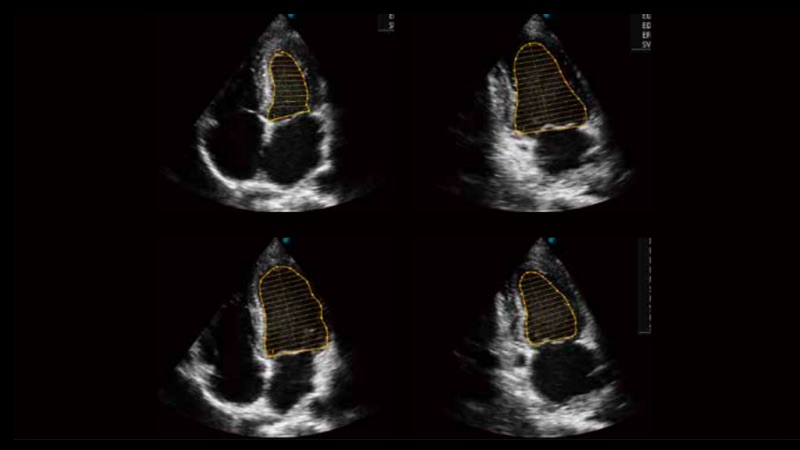

自動(dòng)識(shí)別收縮和舒張末期心肌內(nèi)膜,自動(dòng)計(jì)算射血分?jǐn)?shù)EF值。